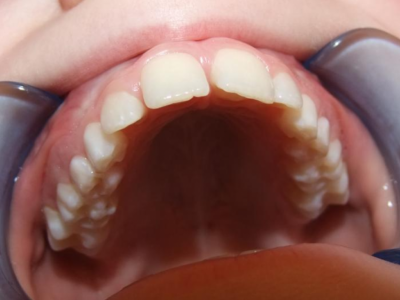

Behandeling Heleen

eindfoto

Leeftijd bij aanvang: 9 jaar

Leeftijd bij retentie: 11 jaar